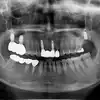

After

임플란트 수술받았는데 안아프게 잘해주시고 원장님과 선생님들 모두 너무 친절하게 해주셔서 좋았습니다 수술비도 너무 가성비가 굿인거 갔습니다 매우 만족합니다

김**

2024-07-05